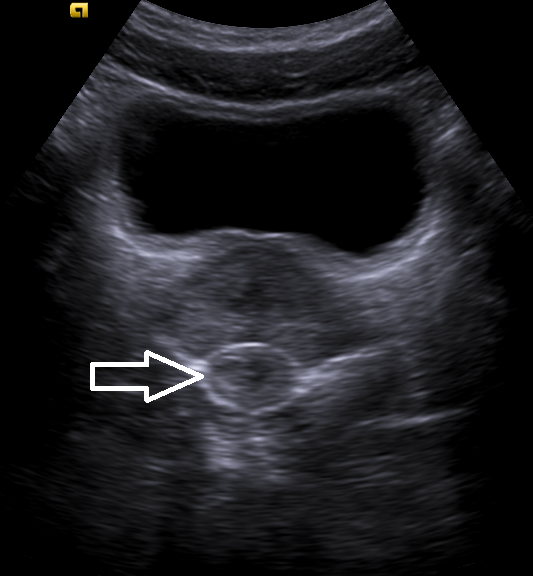

#POCUS image of the day:

Focused clinical question: rule out urinary obstruction

Anything notable on this image apart from presence or absence of hydronephrosis?

#MedEd #FOAMed #Nephpearls

@NephroP Hígado graso, y doble sistema colector en polo inferior de riñón derecho